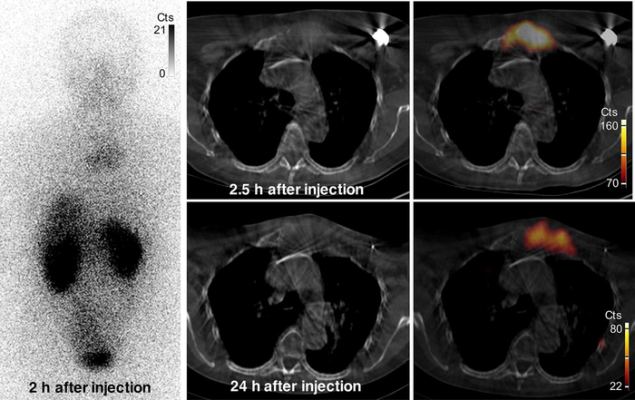

Images of uptake in bone metastasis in patient 2. Anterior whole-body (left) and SPECT/CT (right) images show uptake of 131I-GMIB-anti-HER2-VHH1 at level of large lytic bone metastasis, with soft-tissue component at sternal bone both at 2.5 h and at 24 h after injection. Small differences in area of uptake are explained by differences in patient positioning (arms up at 2.5 h and arms down at 24 h, to maximize patient comfort). Cts = counts. Image created by M. Keyaerts, University Hospital of Brussels (UZ Brussel), Belgium.

In the study, six healthy volunteers and three HER2-positive breast cancer patients received injections of 131I-GMIB-Anti-HER2-VHH1. Vital signs and bloodwork, as well as open-ended questions, were used to assess the safety of the radionuclide. Whole-body imaging was conducted to ascertain biodistribution information and the resulting image data determined the dosimetry. In the three subjects with breast cancer, imaging was also used to measure tumor uptake.

131I-GMIB-anti-HER2-VHH1 was found to be safe and stable after administration and to clear rapidly from the blood in healthy volunteers. The tracer accumulated in metastatic sites of patients with HER2-positive breast cancer.